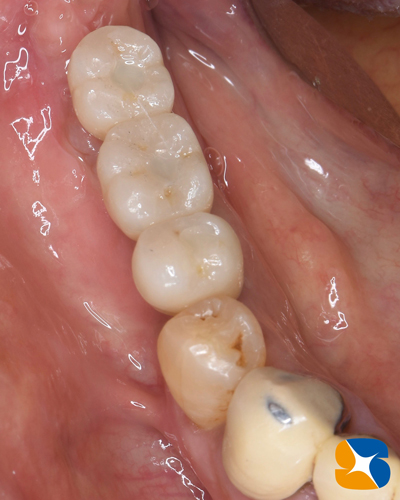

奈良 生駒 石切 インプラント 寝ながら無痛インプラント 良心価格 10年保証 再生医療 インプラントの施術から3ヶ月後の様子。セラミックで出来たネジ固定式の白い奥歯が完成しました。

奈良 生駒 石切 インプラント 寝ながら無痛インプラント 良心価格 10年保証 再生医療 奈良 生駒 石切 インプラント 寝ながら無痛インプラント 良心価格 10年保証 再生医療 常時ー静脈麻酔鎮静 再生医療 良心的価格 石切 生駒 奈良 インプラント特化 使用インプラント:USAオステム社製 TⅡ-SA 左端から長さ8.5,10,11.5㎜の順。太さはいずれも直径4㎜。